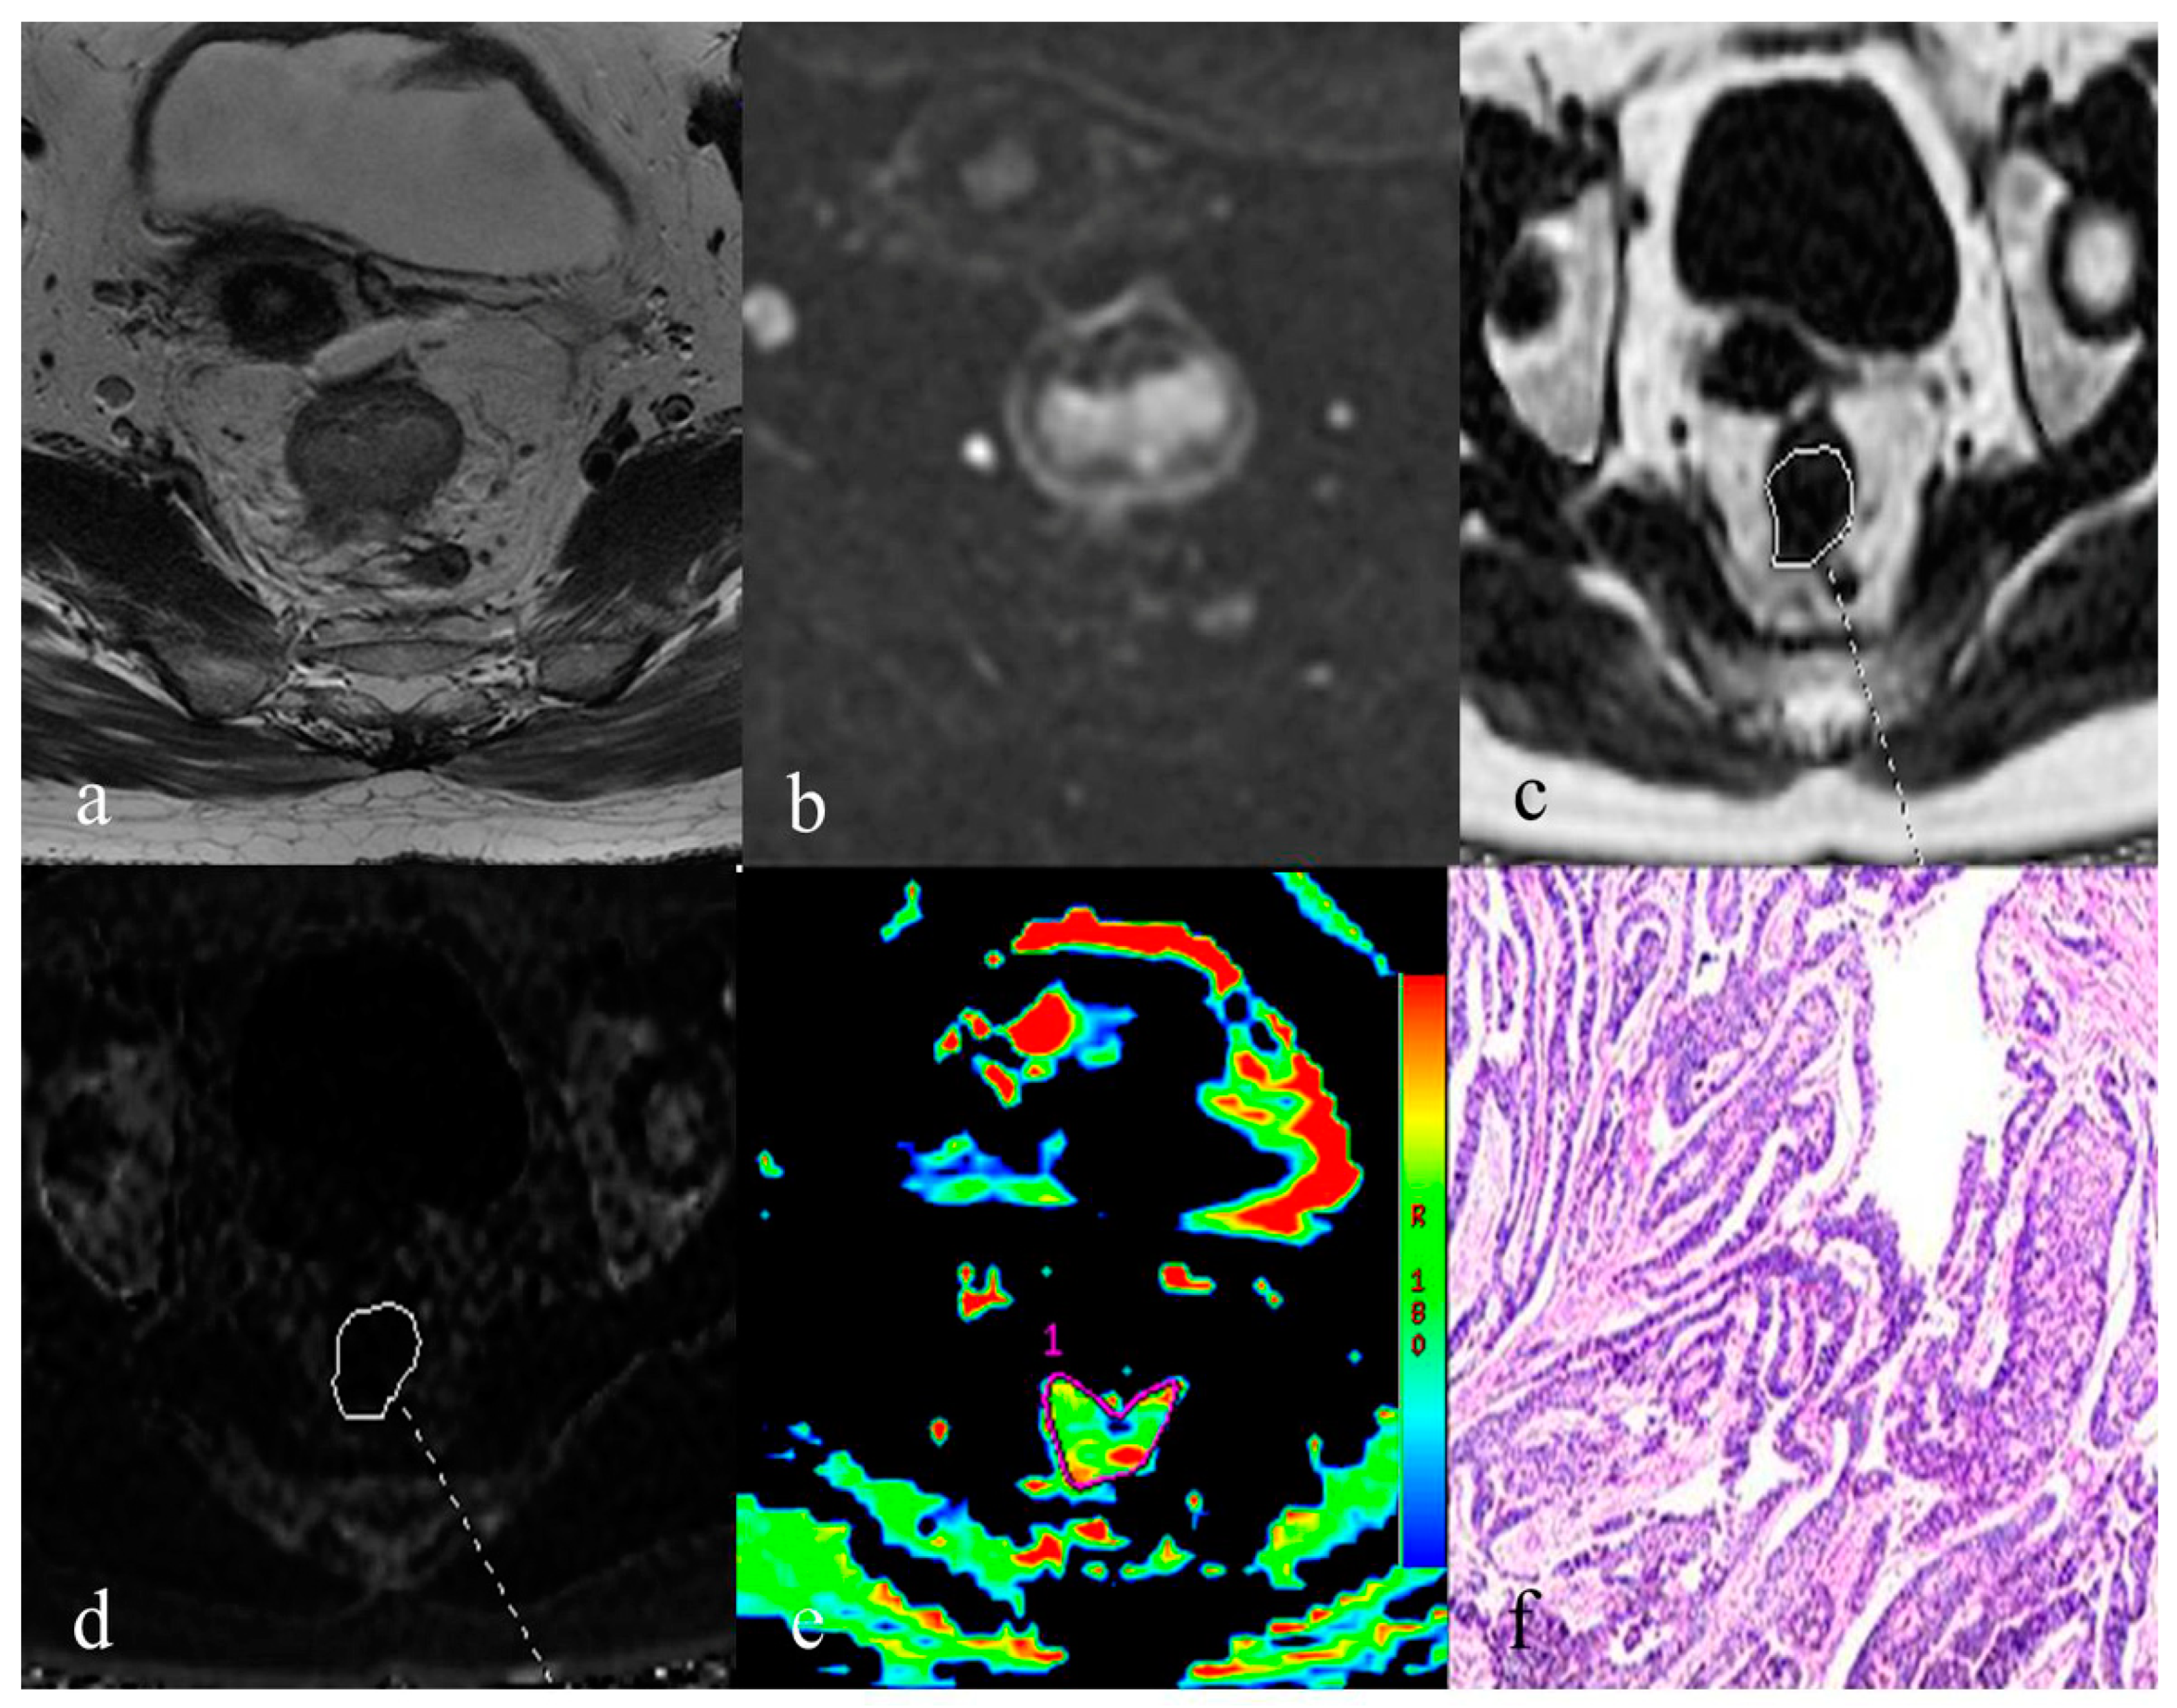

2.3. Image Processing and Analysis